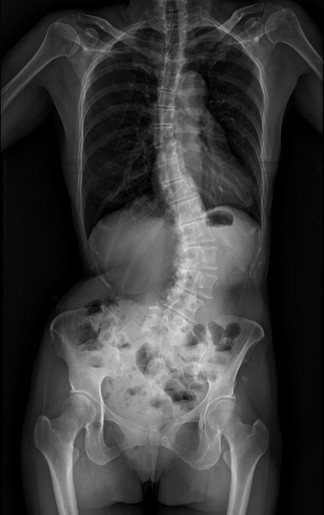

50多歲的黃小姐,年輕時曾被健檢醫師提醒脊椎側彎,多年來不以為意,直到近兩年伴隨脊椎劇痛、下肢麻痺與腫脹,夜晚經常因疼痛而失眠。症狀仍持續惡化,甚至到舉步維艱,已影響工作與生活品質。經友人推薦至臺中市立老人復健綜合醫院(下簡稱 中醫大市醫)骨科就醫,由微創脊椎中心助理副院長張建鈞醫師評估後,決定接受3D導航微創矯正手術。術後從47度矯正至10度,身高增加約5公分,25年的宿疾大幅改善,終於能安穩入睡。

張建鈞醫師指出,患者因長期未治療,脊椎側彎角度已達48度,屬中重度退化性脊椎側彎,加上合併二尖瓣膜脫垂心臟病史,進行傳統開放式手術風險極高。經完整影像評估與跨科討論後,醫療團隊建議採取「微創前開3D導航矯正手術」,在不大幅破壞背部肌群的情況下,從側邊小切口進行矯正與支撐重建。手術後恢復快速,術後4至5天即順利出院,疼痛明顯減輕。黃小姐笑說,術後穿著背架反而帶來前所未有的安全感,甚至捨不得太快卸除。

共同執行手術的骨科部副部長林琮凱醫師進一步說明,脊椎側彎(Scoliosis)是指脊椎向側面異常彎曲,並伴隨椎體旋轉變形,並非單純姿勢不良。醫學上以Cobb角度作為判斷依據,超過10度即可診斷為脊椎側彎。若長期未處理,可能導致慢性疼痛、神經壓迫,甚至影響內臟功能。常見類型包含幼年型、非特異型、退化性、神經肌肉型等,其中退化性脊椎側彎多發生於中老年族群,容易被忽略。